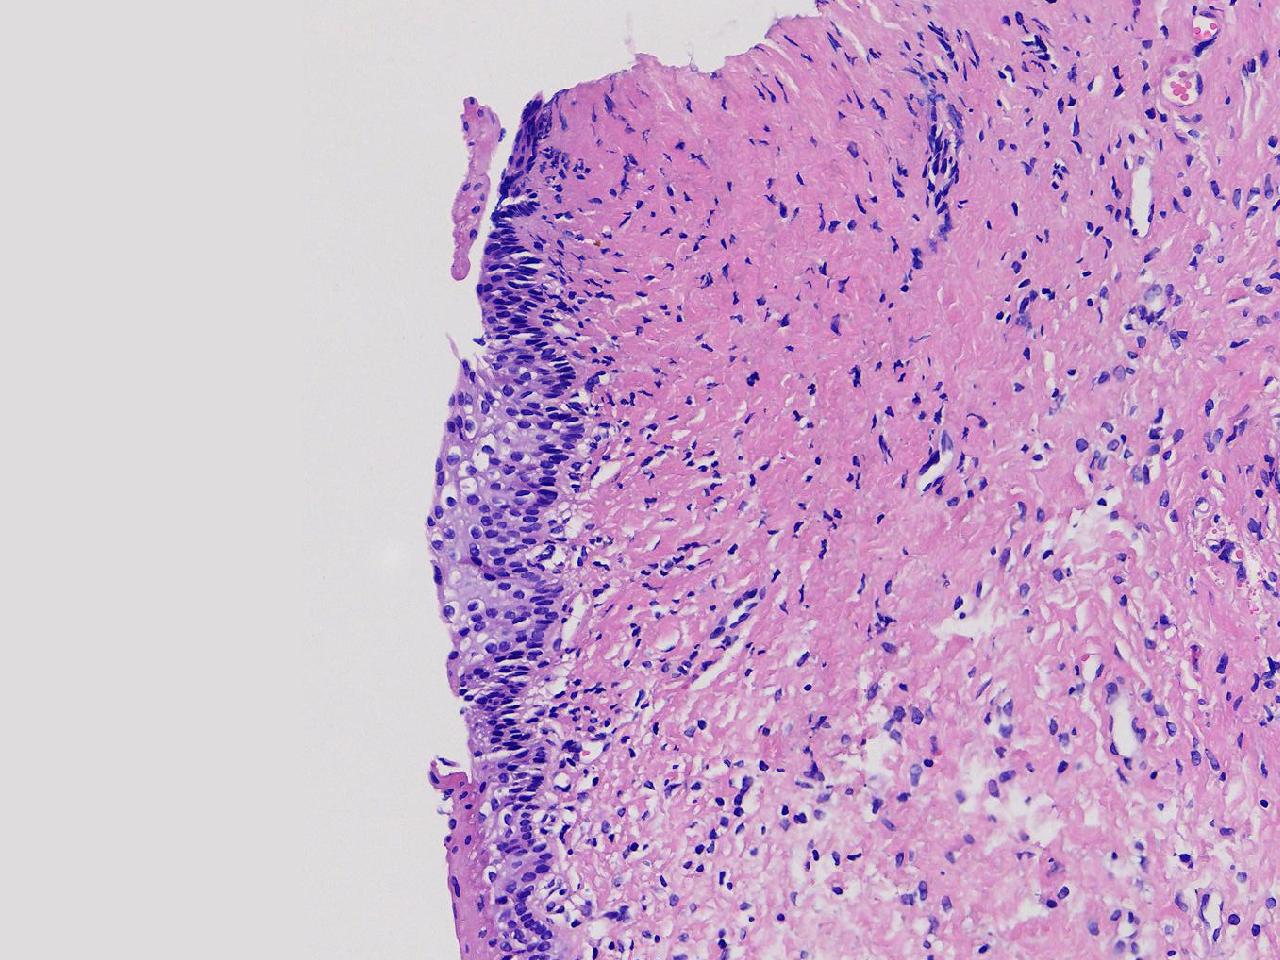

萎缩性? CIN1级?

女,64岁,宫颈活检,HPV不详。

宫颈活检

慢性宫颈炎

萎缩